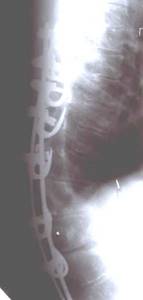

| Больной Т-ов, 16 лет Сколиоз IV степени. До операции |

|

| Внешний вид больного на 10 день после операции |